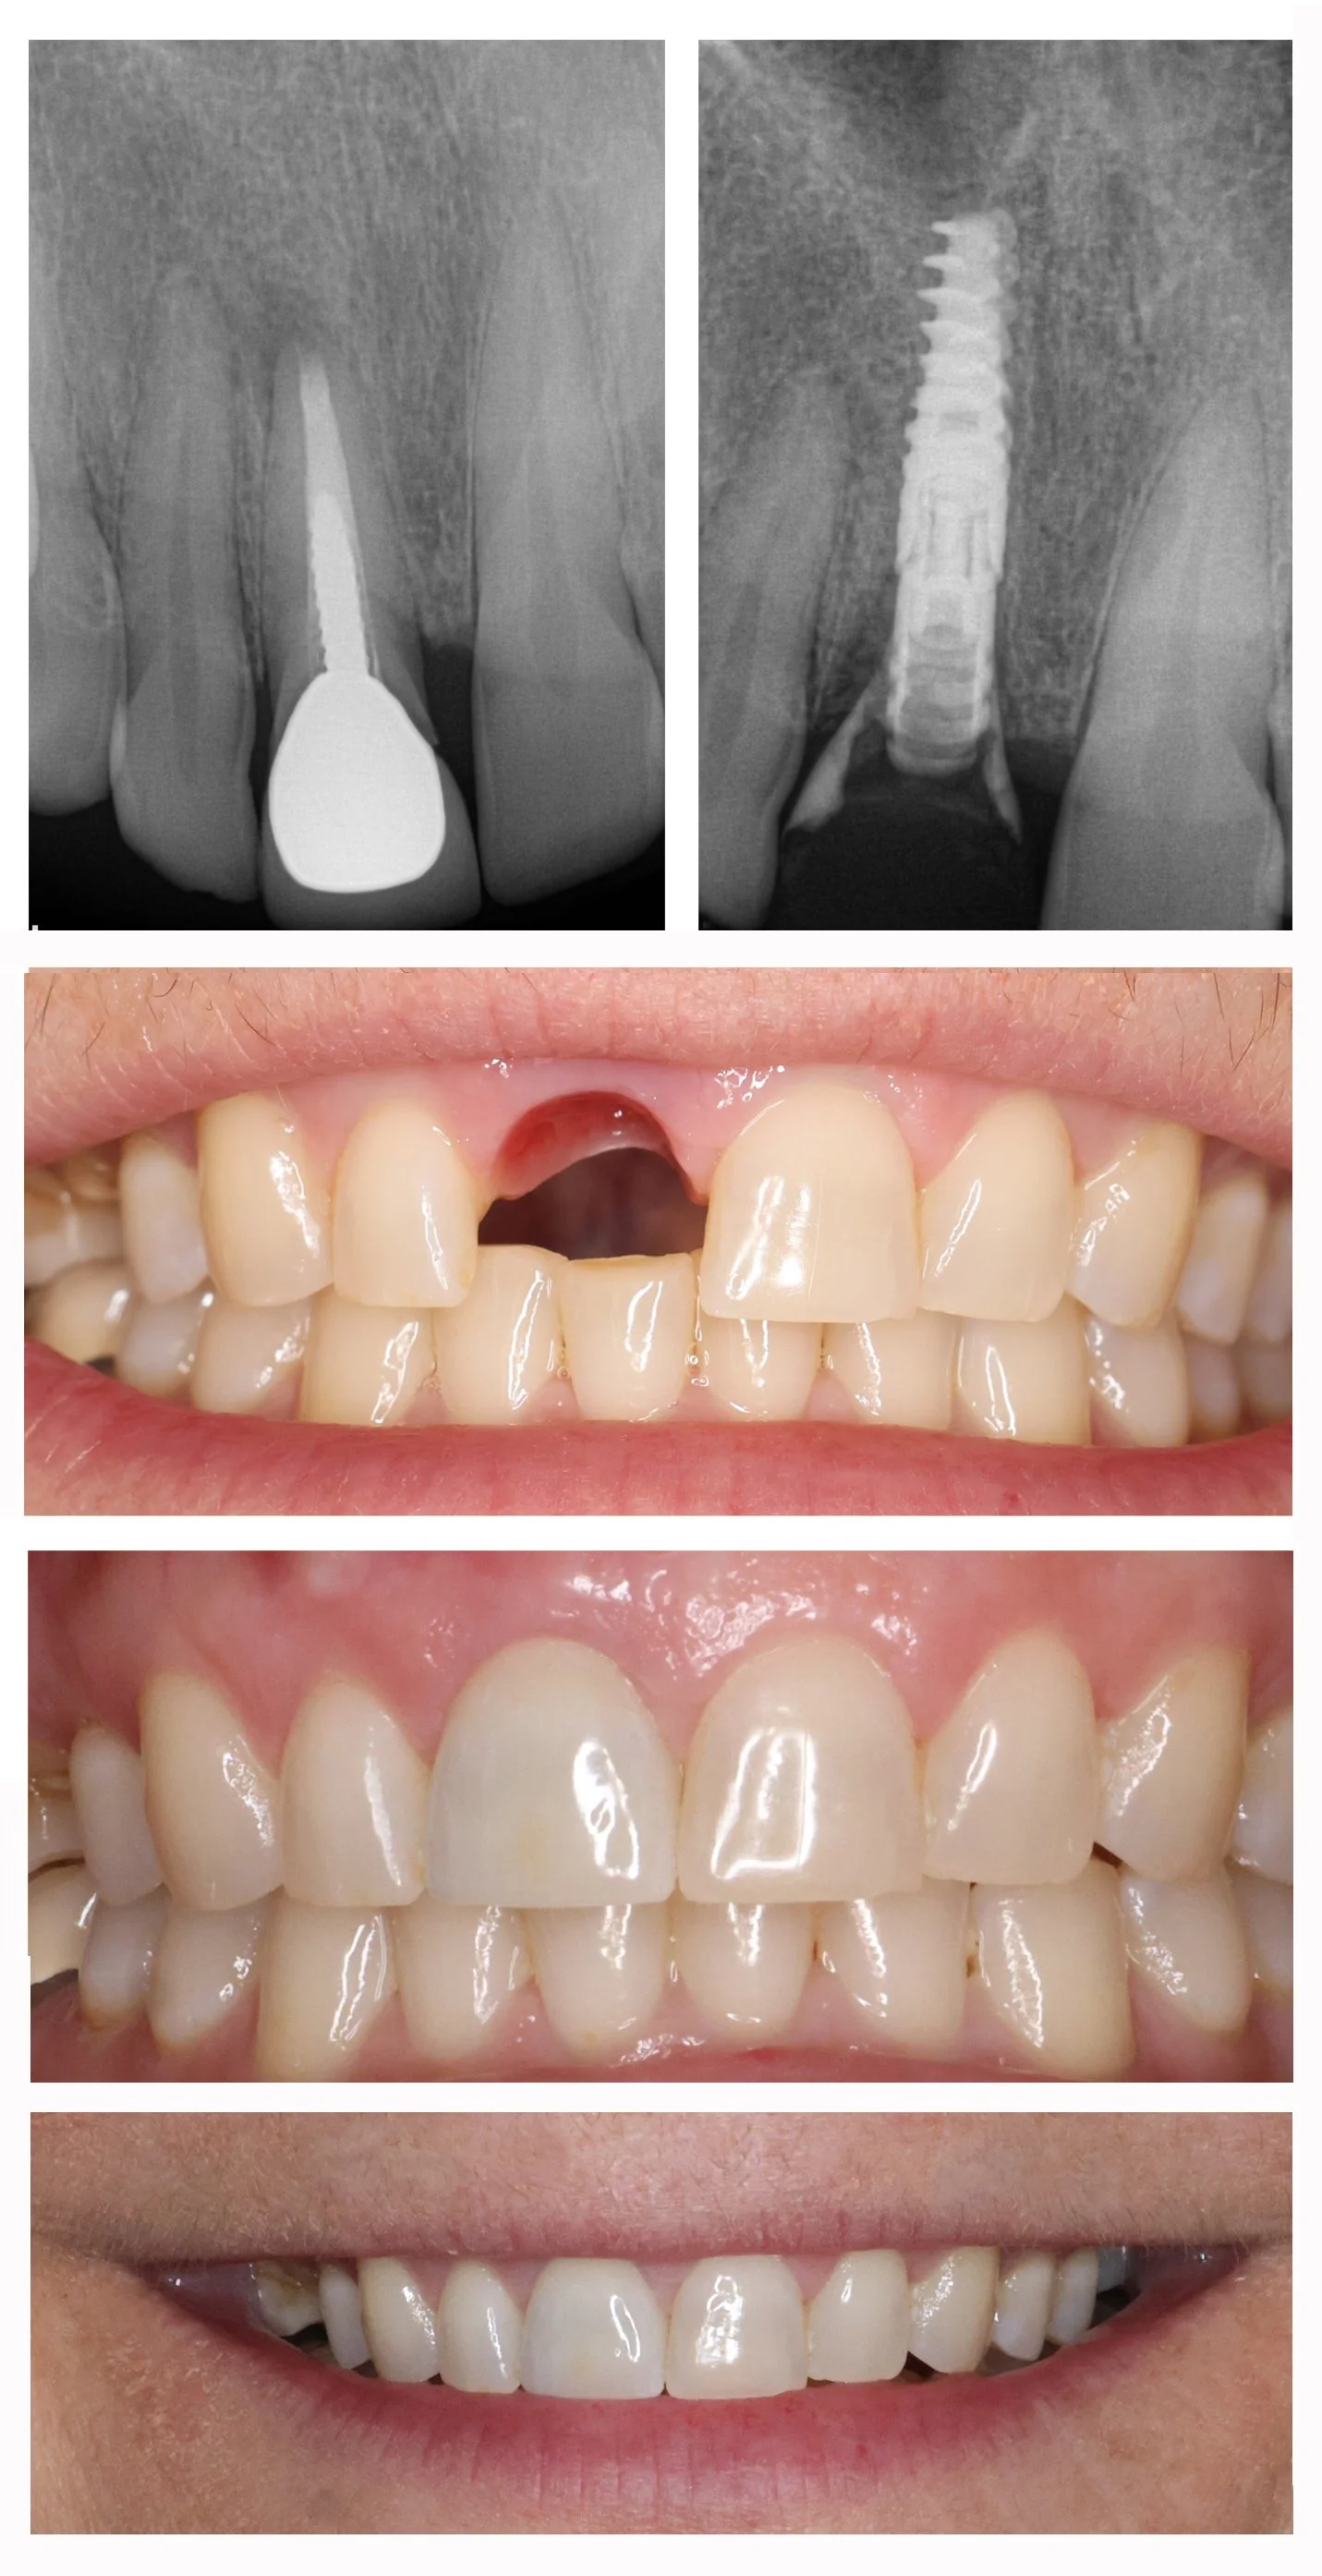

Dental Implants

With the newest technology and products, we can provide a predictable solution for tooth loss.

Before and after implant placement of front tooth, restored with custom crown

Tooth replacement with implant and crown